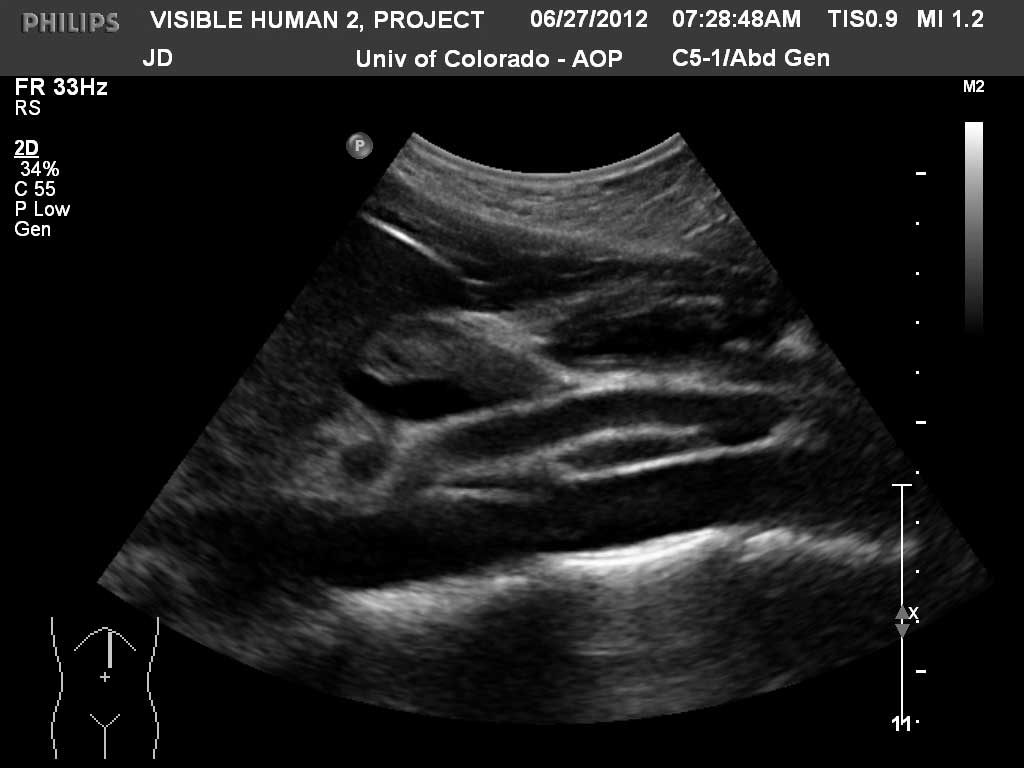

Long (Sagittal) Abdomen

Aorta

Superior Mesenteric Artery